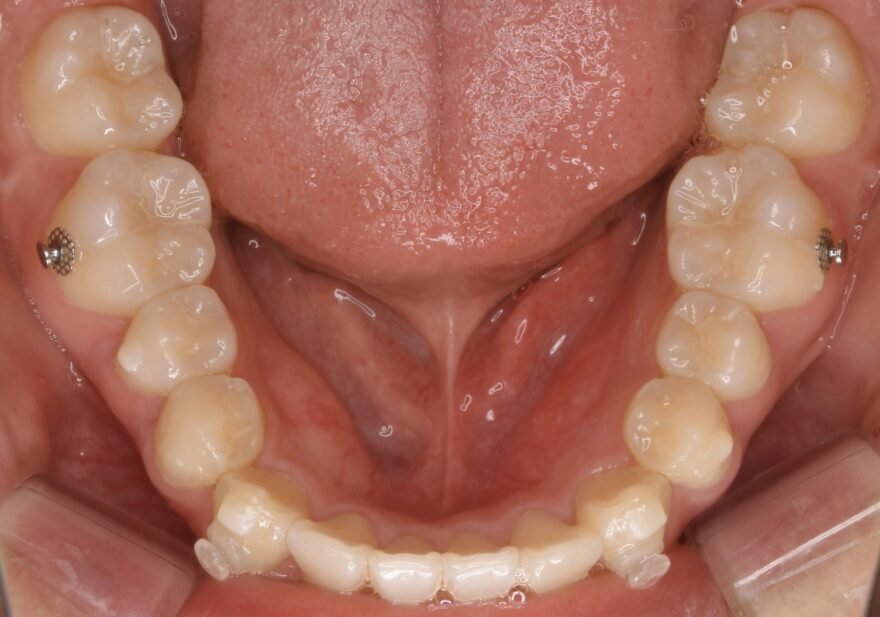

治療中の口腔内写真

インビザラインと他社製マウスピース矯正との違いにアタッチメントがあります。

歯の表面に付与する白くて小さい突起がアタッチメント。

アタッチメントとマウスピースが噛み合うことで、

・回転

・垂直移動

・水平移動

などといったマウスピース単体では苦手とされる、歯の3次元的な移動が可能となります。